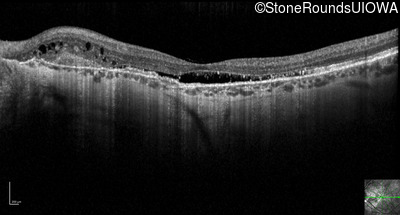

Optical Coherence Tomography - Right - 20/20 -3 sc

Exemplar / OCT Stack